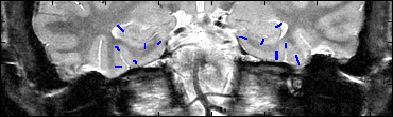

This is an example of one subjects demarcation. The A/P slice is slice

3.

8